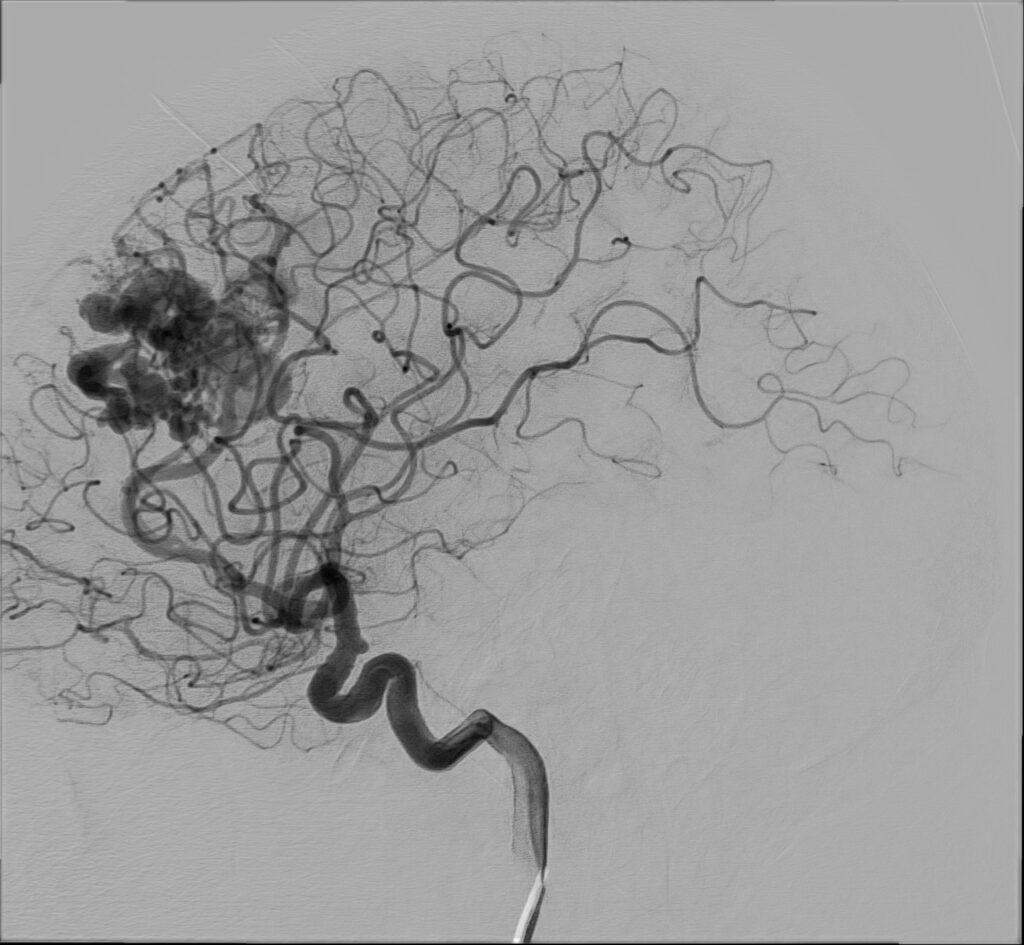

47-letnia kobieta z wywiadem krwotoku z malformacji tętniczo-żylnej (AVM) w prawej okolicy czołowej kilka lat temu, po kilkukrotnej embolizacji zmiany, zarówno w Polsce, jak i w Holandii, została przyjęta do Oddziału z powodu drugiego w życiu krwotoku ze zmiany naczyniowej.

W badaniu CT widoczne jest rozległe krwawienie dokomorowe.

W badaniu angiografii subtrakcyjnej widoczne jest rozległe (ponad 3 cm) gniazdo naczyniowe zaopatrywane z tętnicy przedniej mózgu prawej, zarówno z gałęzi okołospoidołowej, która oddawała 2 tętnice żywiące, jak i gałęzi korowych, oddając jedno naczynie żylne drenujące do zatoki strzałkowej górnej.

W tym przypadku chora została zakwalifikowana do leczenia operacyjnego – kraniotomii czołowej przystrzałkowej i resekcji zmiany naczyniowej. Zmiana została usunięta, bez nowych deficytów neurologicznych. W kontrolnym badaniu DSA nie uwidoczniono resztkowej przetoki naczyniowej, co jest sukcesem operacyjnym.